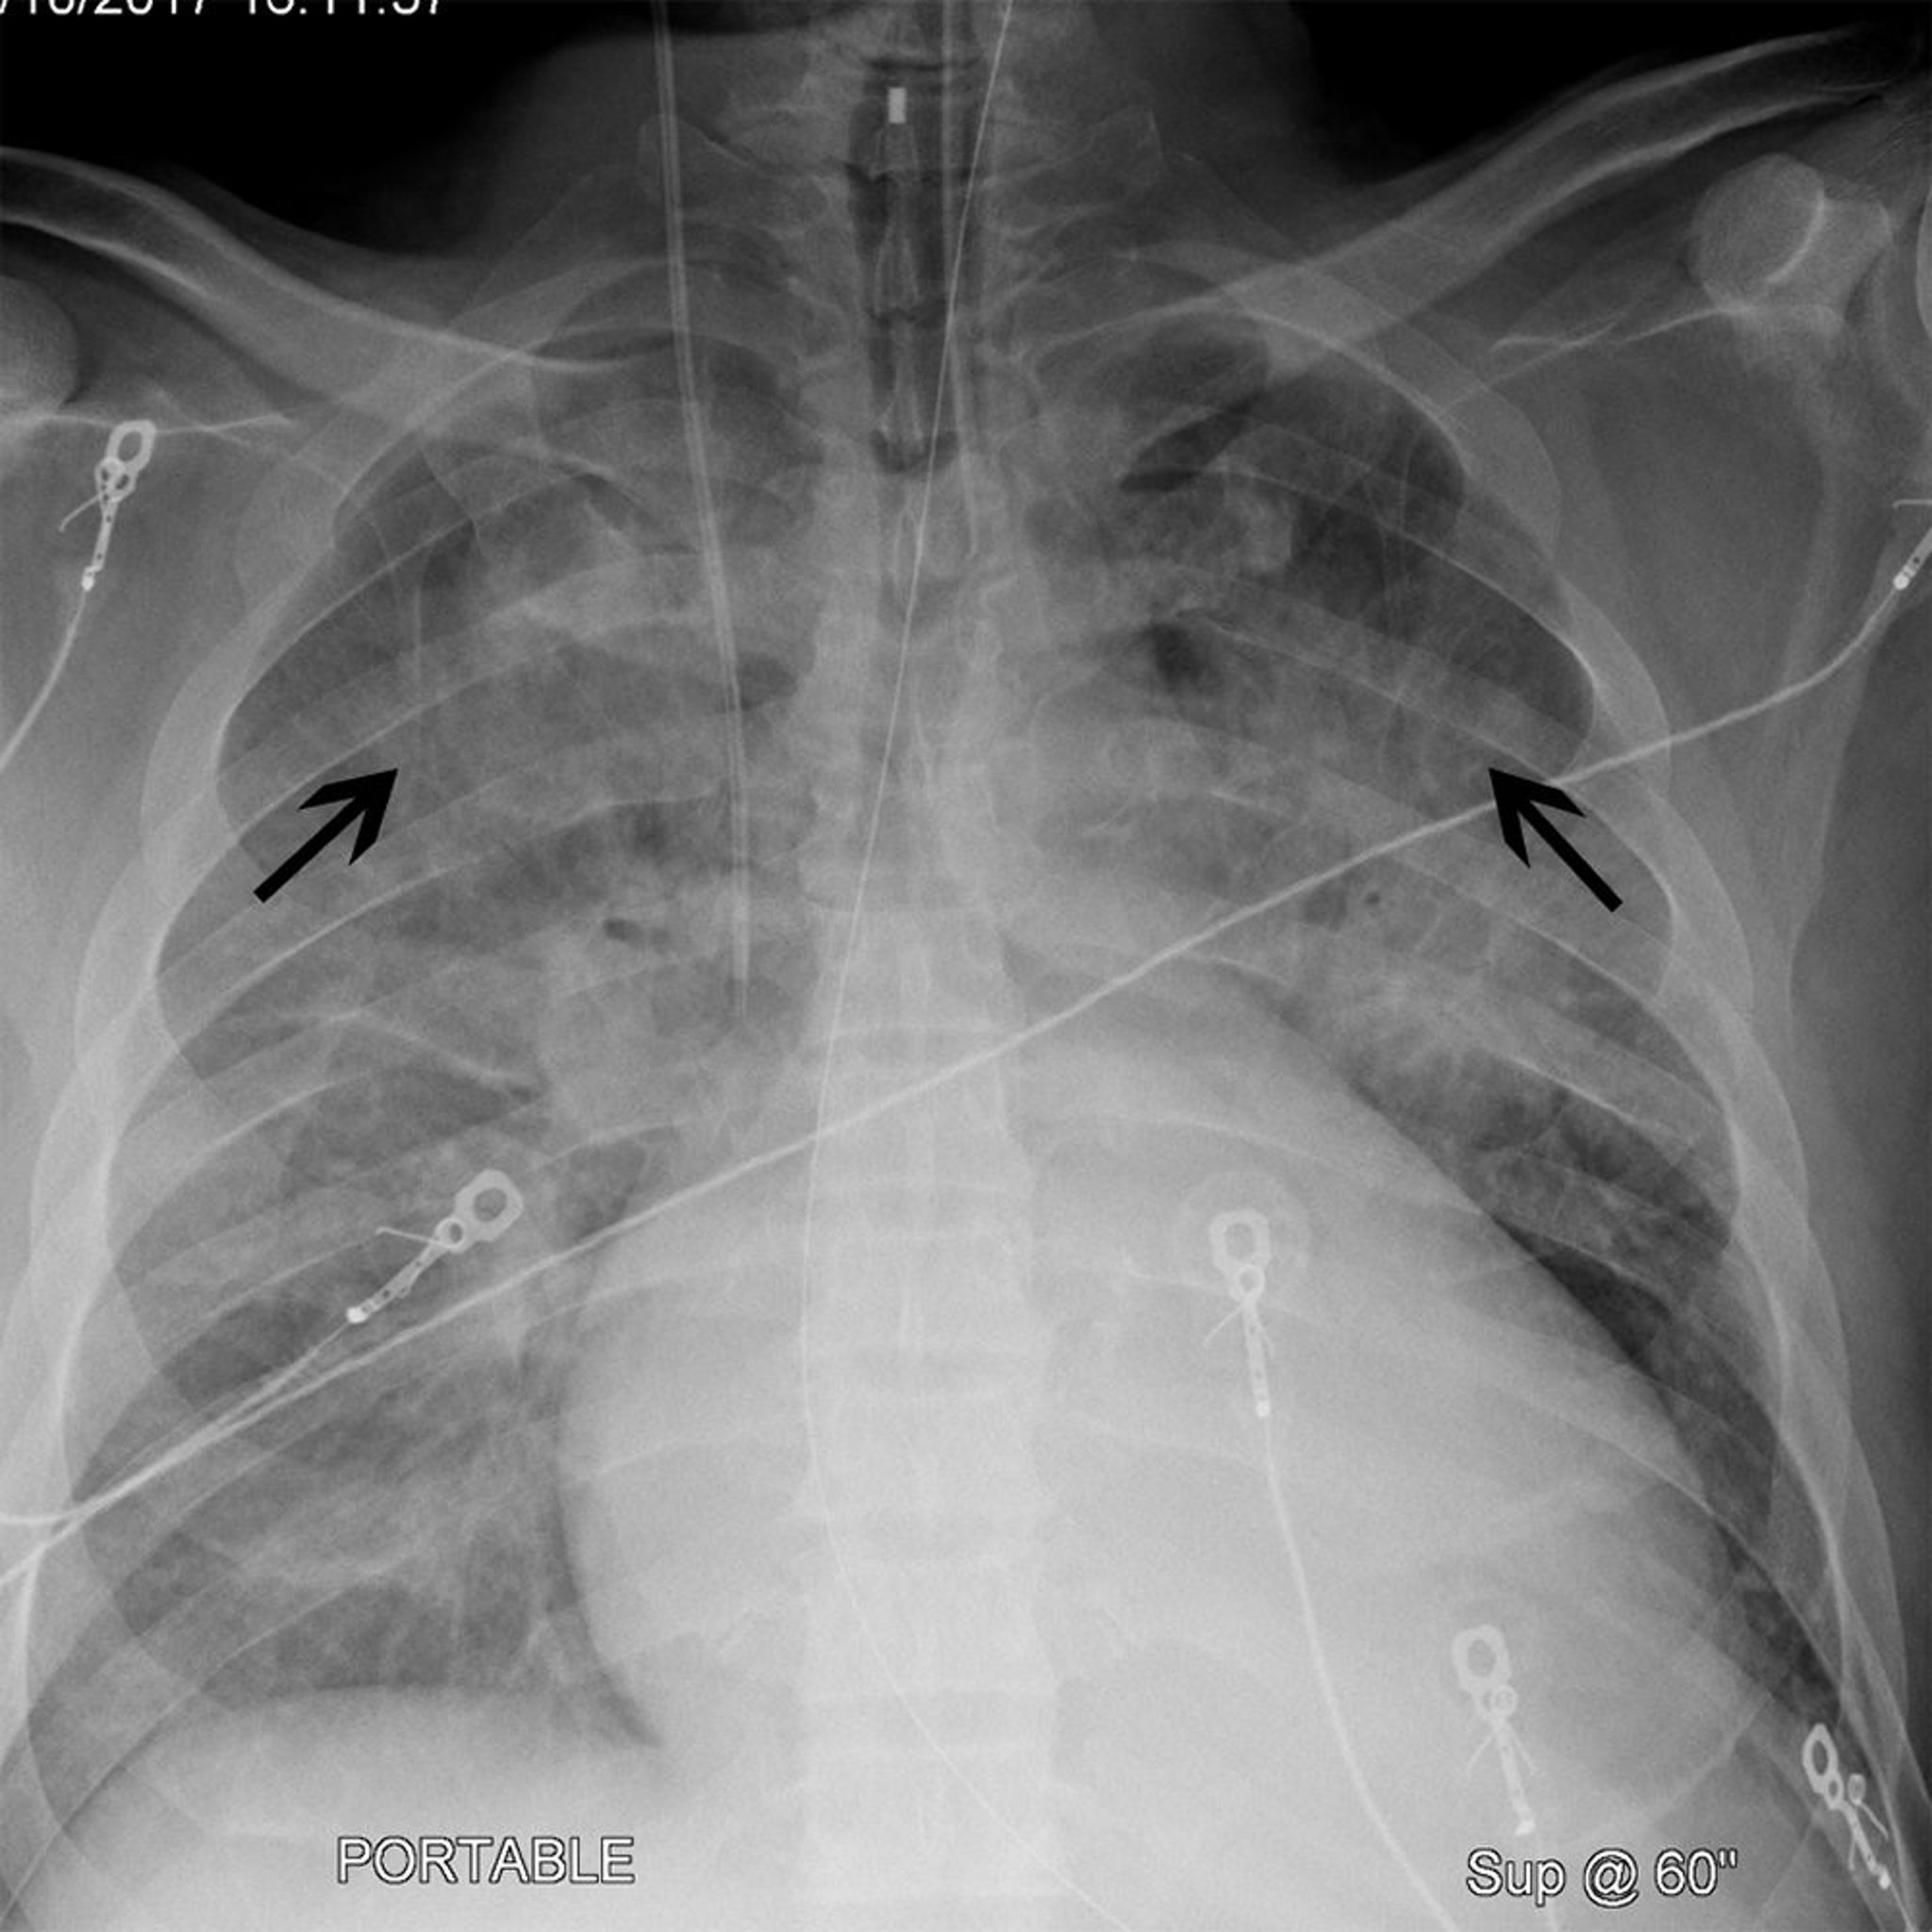

Radiografia do tórax de um paciente com cardiomegalia e cefalização

Esse paciente tem cardiomegalia (a largura da silhueta cardíaca é > 50% da caixa torácica em uma radiografia de tórax posterior-anterior). O paciente também apresenta cefalização (setas pretas) em que os vasos pulmonares do lobo superior se tornam mais proeminentes. Esses achados costumam ser vistos em pacientes com insuficiência cardíaca.